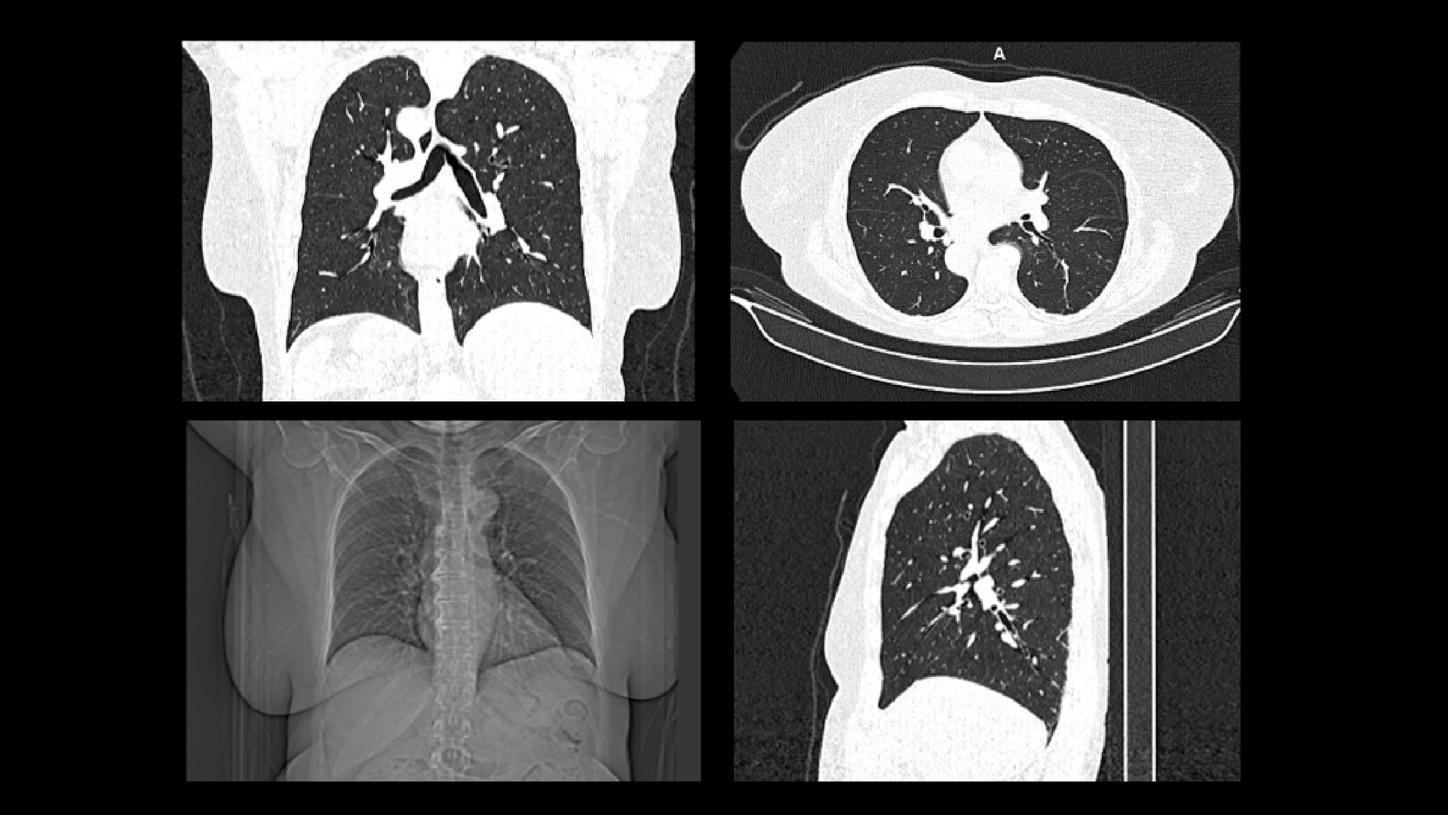

Detecting early-stage lung cancer with low-dose CT scanning can dramatically improve the long-term survival rate of lung cancer patients. A study4 shows that patients diagnosed with lung cancer by low-dose CT screening have a 20-year survival rate of 81%. If diagnosed in the earliest Stage I and if adequate therapy has been applied, long-term survival was 95%. This emphasizes the benefit to establish screening programs for earlier detection. Our ultra-low-dose CT scanners and AI tools help you deliver confident and accurate screening outcomes.

Our CT scanners come with advanced technology inside that allows ultra-low-dose, non-contrast chest CT scans for a screening examination.

A smart augmented reading aid and AI-powered workflow solution help reduce repetitive tasks and supports diagnostic precision by detecting and highlighting possible nodules.

Through functional examinations such as tissue perfusion or iodine quantification, our SOMATOM CT scanners enable early assessment of lung tumor response or disease progression.